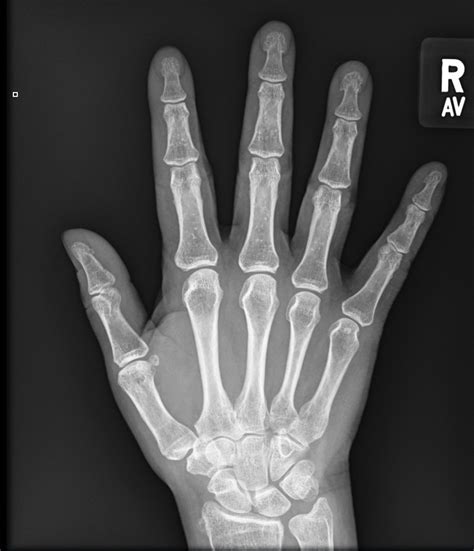

Normal Hand X Ray Right

Normal Hand X Ray Right. Normal ap view of the right hand in an adult patient. A systematic approach will help those.